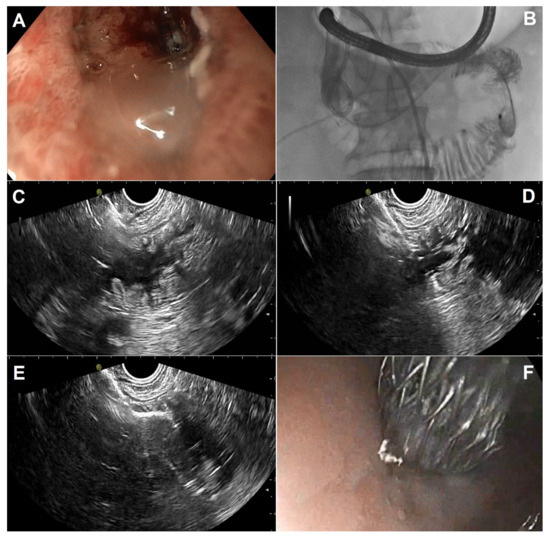

Figure 3.

Standard steps in performing EUS-guided gastroenterostomy in a patient with a short and incomplete duodenal stricture leaving a small opening: (A) jejunal loop identification after its proper distension with saline mixed with contrast and methylene blue; (B) cystotome tip (arrow) advancement after cut with pure current for obtaining intrajejunal access; (C) distal flange deployment under EUS guidance; (D) endoscopic view of the proximal flange after deployment under EUS/endoscopic control, with spilling of blue-colored fluid indicating proper stent placement.